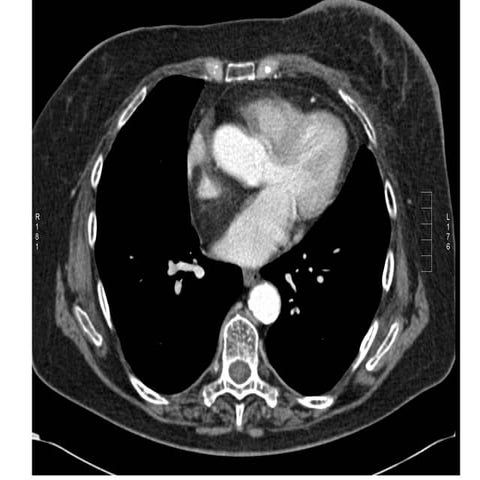

40 year old